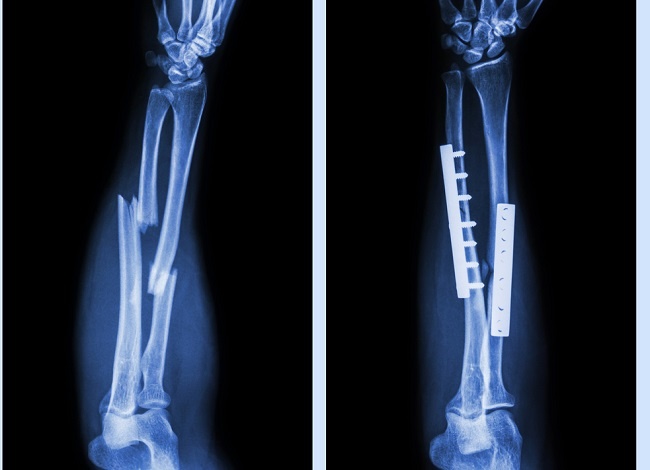

Perlukah membuang besi atau implan? û Dr Ahmad Mahyuddin | The Malaysian Medical Gazette

Perlukah membuang besi atau implan? û Dr Ahmad Mahyuddin | The Malaysian Medical Gazette

Untuk operasi patah tulang kaki

Untuk operasi patah tulang kaki

Lihat Hasil X-ray Bikin Ngilu! Begini Ternyata Patah Tulang Humerus Marc Marquez, Pelat dan 12 Baut Titanium Terpasang - GridOto.com

Lihat Hasil X-ray Bikin Ngilu! Begini Ternyata Patah Tulang Humerus Marc Marquez, Pelat dan 12 Baut Titanium Terpasang - GridOto.com

Plat Logam Pasca Fraktur : Perlu Diangkat Atau Tidak - Alomedika

Plat Logam Pasca Fraktur : Perlu Diangkat Atau Tidak - Alomedika